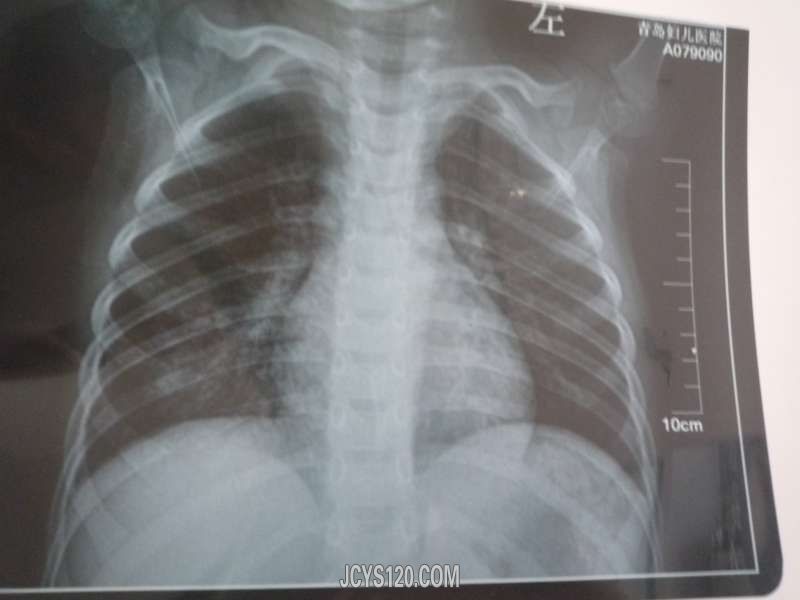

现病史:小患者于13天前出现发烧最高体温38.9,每天下午发烧,在家家长自行服药,头孢拉定颗粒,护彤小儿感冒颗粒,小儿布洛芬等,每次服药后大汗淋漓热退,精神不减,饮食可,3天后还是发烧又到乡镇医院就诊,乡镇医院诊断:“上感”嘱其在家继续服药观察,7天后还是始终发烧不减,每天下午晚上都发烧,38-38.5度又到市医院就诊化验血常规,肺部正侧位片均正常,于是就回家在其诊所输液治疗五天:阿奇霉素 炎琥宁(口服头孢克圬片,小柴胡颗粒 ),输液5天始终每天下午发烧38度左右,开始伴有咳嗽(咳嗽次数逐渐增多,伴有粘痰,小儿不会吐痰伴有痰鸣音),又来我诊所就诊。

查体:体温38度 心率106次 ,发育正常,精神可,查体合作,颈部无抵抗,全身皮肤黏膜无黄染,无出血疹,浅表淋巴结无肿大,头颅五官无畸形,双侧瞳孔等大等圆,对光反射好,双肺呼吸音粗,有痰鸣音,心脏不大,心音正常,无杂音,心率快,全腹部无压痛及反射痛,腹软,无气过水声,肠鸣音正常,肝脾未触及,双下肢无水肿,生理反射存在,病理反射未引出。

我给患者查完体分析病情还是进一步复查血分析,C-反应蛋白,支原体()肺部正侧位片,排除“肺炎”

对于诊断与治疗大家怎么看?此患者今日才退热,体温恢复正常,发烧13天。第一次检查:血分析,肺部正侧位片显示大家怎么看?输液5天白细胞升高大家怎么理解的?欢迎各位朋友发言!